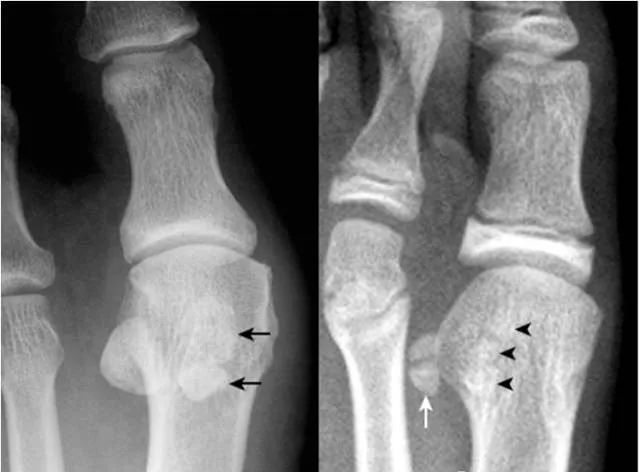

32.拇趾撕脱骨折:

该例为陈旧性撕脱骨折。拇趾外侧基底部部分撕脱,虽游离骨片(箭)边缘清晰,但与基底部有很好的对合,可与关节旁骨相鉴别。

33.籽骨骨折:

拇趾外侧籽骨形态不完整,内侧见透亮线(箭),两部分骨对应缘不规整,无硬化缘,与二分籽骨的边缘骨质致密不同。内侧籽骨完整(箭头)。